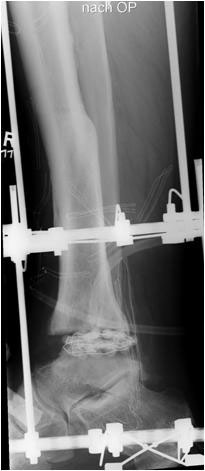

• Revision einer gescheiterten Fusion des OSG/ USG (Abbildung 3, Abbildung 4).